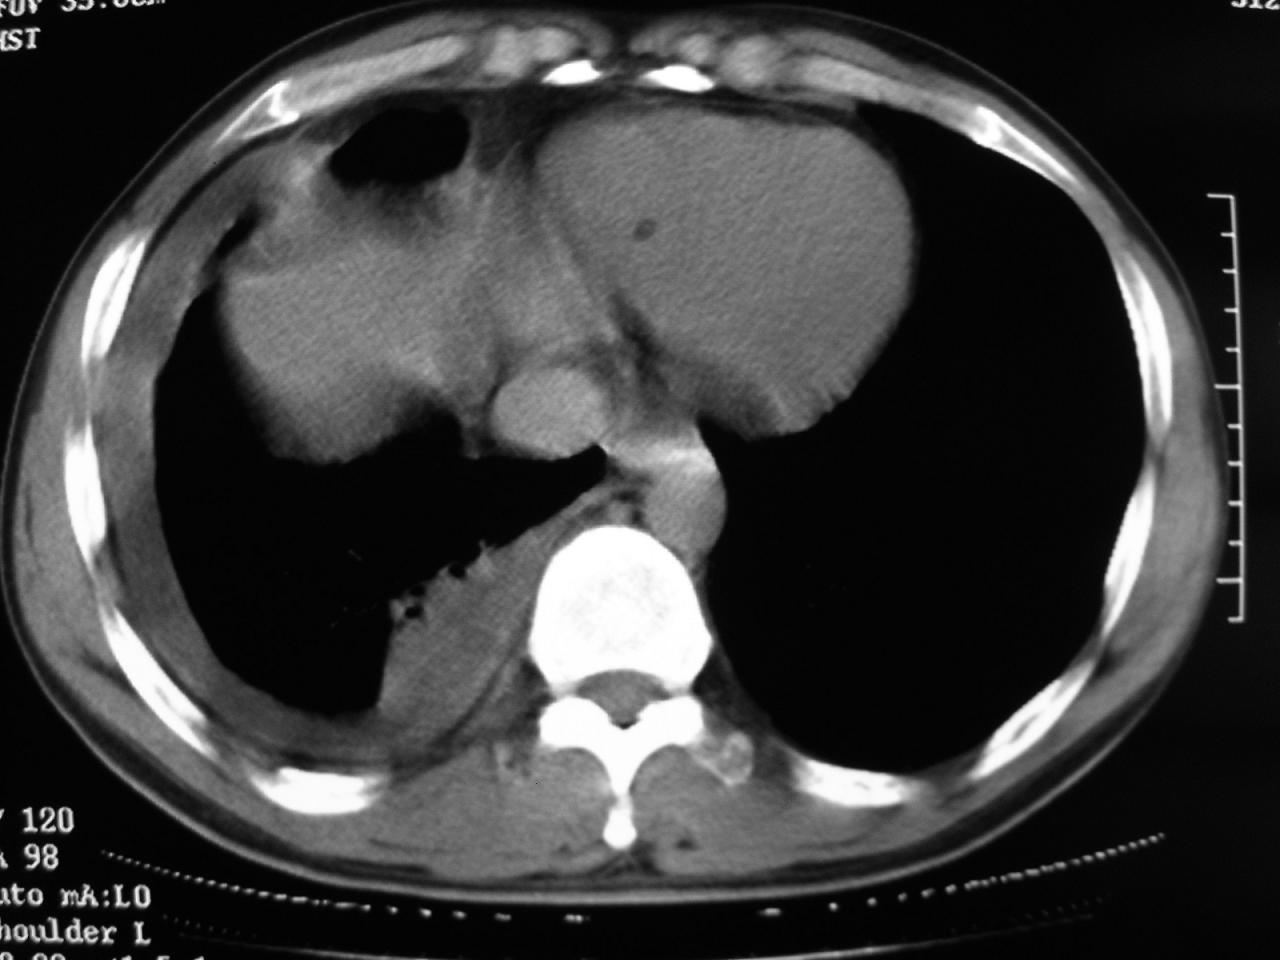

男,32岁,多年前右上肺结核,近期胸部不适,ct检查次序如上,上传主要层面,纵隔未见明显肿大淋巴结。

本人初次(2008年12月20日ct片)诊断为右上肺结核伴右侧胸水!保守治疗后,遂复查ct胸水逐渐减少!最后(2009年05月18日)诊断为右上肺结核,右侧胸水吸收后伴包裹形成!从逐次ct检查上看,胸水吸收好转,只是从2009年05月18日ct片看到一个胸膜结节。临床医生及某肿瘤医院认为2009年05月18日ct片,右后胸壁结节,考虑为胸膜肿瘤!

本人还是倾向于右后胸壁的局限性包裹,胸膜结节密度不均匀,其内可见低密度区,考虑是由胸水吸收后胸膜增厚、粘连及周围肺组织包裹形成的征象;不倾向于胸膜肿瘤的诊断。